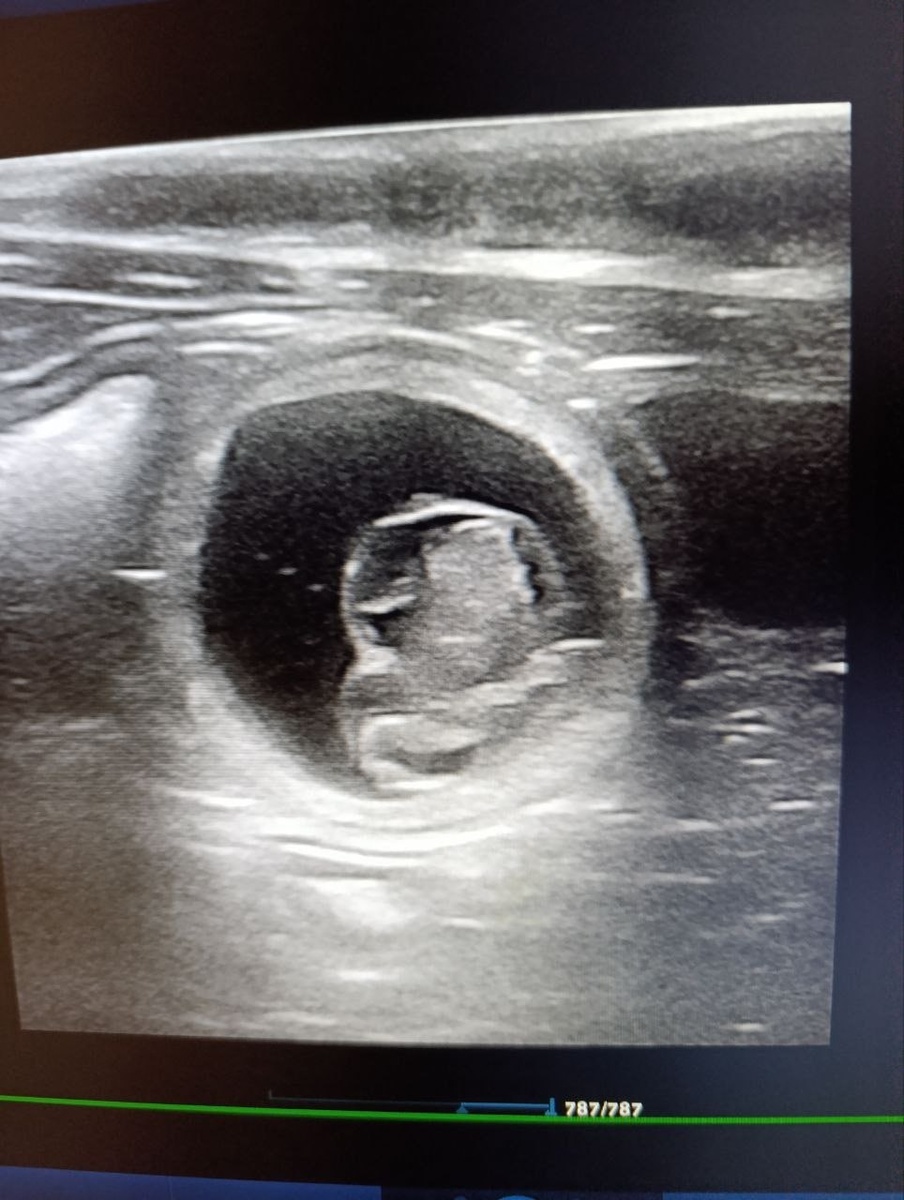

В конце ноября ждем малышей от красивой пары 😃

Тихона (VinniMur Tikhon) и Зазнобы (VinniMur Zaznoba) ❤️